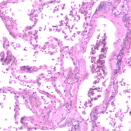

Ms. Stacey McCord represented the USTUR at the 2011 Annual Meeting of the European Dosimetry Group (EURADOS), Prague, Czech Republic, February 7-9, 2011. Ms. McCord participated in the Working Group 7 (WG7) on “Internal Dosimetry” and attended the Winter School on “Radiation Protection for Medical Staff. Her presentation to WG7 titled, “Microdistribution and Long-Term Retention of 239Pu(NO3)4 in the Respiratory Tract: A progress report” can be downloaded from the following link.